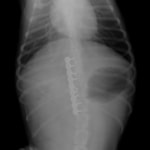

症例:交通事故による椎体脱臼

柴犬:9歳、避妊雌

交通事故直後、胸腰部に激しい疼痛、両後肢に完全麻痺を認め、シェフシェリントン徴候を呈していました。レントゲン検査において、第11-12胸椎間の脱臼が認められました。

脊髄の減圧、脊柱管の再構築・安定化を目的に、片側椎弓切除術およびMatrixMANDIBLE Plateによる椎体固定を実施しました。

隣接椎体を架橋するようにプレートを設置しました。

術後レントゲン写真